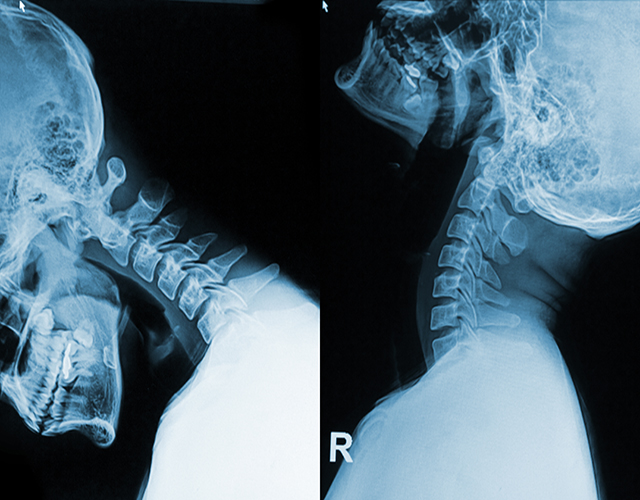

“医生,颈椎反弓是怎么回事?还能不能恢复呀?” 门诊的时候,有不少患者拿着颈椎X线片来询问。

颈椎反弓是颈椎病最为常见的病理基础。一般来说,人的颈椎是呈“C”形生理弯曲的。要是没有这种生理弯曲了,甚至是朝着相反的方向弯曲,这就是颈椎反弓。